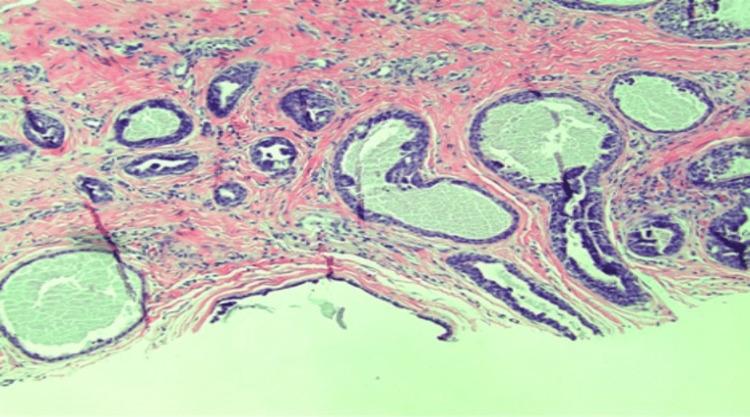

Papillary eccrine adenoma (PEA) is a rare benign eccrine gland neoplasm presenting as a solitary nodule, primarily in middle-aged African American females. Accurate histological diagnosis is crucial due to its potential to mimic adnexal carcinomas. Complete excision is recommended due to its risk of local aggression and recurrence. A 75-year-old Caucasian male with a history of basal cell carcinoma (BCC) presented with a recurrent pink, scaly nodule on the right medial pretibial leg area. Initial biopsy showed benign PEA. The lesion recurred after one year, and a re-biopsy confirmed a tubulopapillary adenoma within a scar. The lesion was excised with a 2 mm margin. PEA is characterized histologically by dilated ducts lined by a dual layer of tumor cells, often with intraluminal papillae structures. Immunohistochemical staining aids diagnosis, with markers such as S-100, carcinoembryonic antigen (CEA), and epithelial membrane antigen (EMA) indicating eccrine differentiation. Differential diagnoses include adnexal carcinomas and BCC with eccrine differentiation. Complete excision is necessary to prevent recurrence.